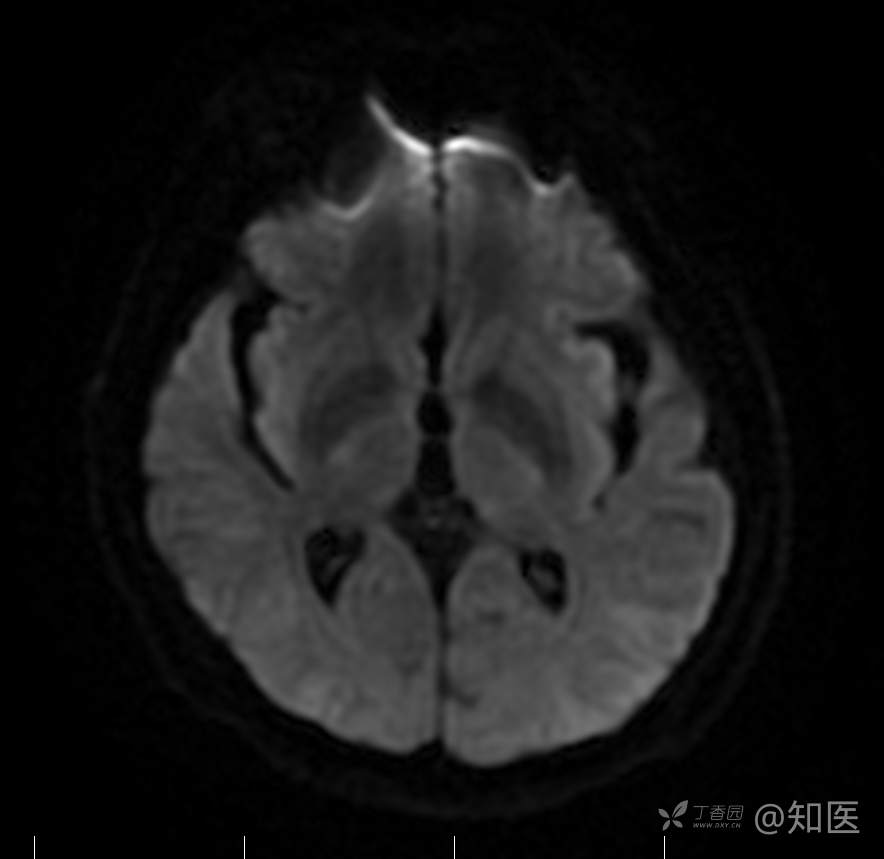

2021-6-15 DWI

2021-06-16日晨查房,患者自觉入院治疗后肢体无力症状较前稍改善,仍有活动后气短,余未诉特殊不适。ALSFRS-R评分:44分(单项均大于等于2分)。血压:123/63mmHg。神经系统查体:GCS 15分,右利手,查体合作,问答切题,粗测智能基本正常。额纹对称,双眼闭目紧,双侧瞳孔等大等圆,直径约3.0mm,对光反射灵敏,眼球运动自如,无眼震,双侧鼻唇沟对称等深,口角无歪斜。悬雍垂居中,双侧软腭抬举良好,咽反射灵敏、转颈、耸肩均一致有力。颈屈肌、颈伸肌力量5级。伸舌居中,无舌肌纤颤及萎缩。双侧岗上肌、岗下肌可见萎缩;双侧三角肌可见偶发肉跳、肌力5级,左侧肱二头肌肌力4+级、右侧4-级,双侧肱三头肌肌力4+级;双手握力可,双手大小鱼际肌及第一骨间肌可见萎缩,左侧明显,左侧手腕背伸力量4级、右侧4+级,双侧拇短展肌肌力4-级,双侧示指伸肌肌力3级,左侧指总伸肌肌力4级、右侧4-级,双侧小指展肌肌力4-级。双上肢肌张力对称减低。左侧肱二头肌反射迟钝、右侧未引出,双侧桡骨膜反射及肱三头肌反射未引出。左侧胸大肌反射阳性、右侧未引出,双侧Rossolimo征阳性、Hoffmann征阴性,下颌反射阴性。腹壁反射未引出。双下肢可见肌肉萎缩,以左侧明显;左侧髂腰肌肌力4级、右侧4-级,双侧股四头肌肌力5级,双足背伸力量3级,左足跖屈力量4级、右足4+级。双下肢肌张力对称基本正常。双侧膝腱反射、跟腱反射迟钝,双侧跖反射消失,双侧巴氏征未引出。右侧大腿外侧肌肉活检瘢痕周围浅感觉缺失,余肢体及躯干深浅感觉正常,共济运动对称正常。颈软,无抵抗,双侧布氏征及克氏征均阴性。辅助检查:微量元素(钙、镁、铁、铜、锌),微量元素测定(铅,镉)[复][2021-6-16 16:11:07]:钙1.19mmol/l;铁9.00mmol/L。急诊电解质七项[复][2021-6-16 10:41:41]:钾3.55mmol/L。血细胞分析+五分类[2021-6-16 9:57:17]:淋巴细胞百分比19.5%。[头颅,扩散成像(DWI)][头颅,磁敏感成像(SWI)][头颅,水抑制成像(FLAIR)][2021-6-16 18:10:50]:1.多发腔梗,脑白质脱髓鞘,脑萎缩。2.DWI:脑实质内未见明显高信号。3.磁敏感成像脑实质内未见明显异常信号灶。MMSE:26分(高中文化水平)。MoCA:23分。ADL评分:14分。ECAS评分:96分(ALS特异67分、ALS非特异29分)。肌电图:提示颈髓、腰髓、胸髓和延髓支配肌肉可见活动期神经源性损害,颈髓和腰髓支配肌肉同时可见慢性期神经源性损害;提示脊髓前角细胞损害可能,请结合临床。心电图大致正常。外送基因检查:TBK1基因杂合子,提示额颞叶痴呆和(或)肌萎缩性侧索硬化症4型。二线主治医师查看患者后示:1.患者基因检查结果显示TBK1基因杂合子,提示额颞叶痴呆和(或)肌萎缩侧索硬化症4型,结合外院影像学检查可见额颞叶萎缩明显,来院后复查头颅FLAIR+DWI+SWI亦提示脑萎缩,量表评估提示认知功能稍减退,ECAS评分基本正常。综上,修正诊断:肌萎缩侧索硬化症(ALS) 额颞叶变性 低钾血症 高血压2级(高危) 多发腔隙性脑梗死。因TBK1基因引起的额颞叶痴呆和(或)肌萎缩侧索硬化症为常染色体显性遗传,患者父亲已逝,母亲健在,诉无明显认知功能障碍或肌肉萎缩等表现,建议患者母亲抽血送检,进一步明确致病基因来源,必要时患者子女也可行基因检查进一步明确。2.患者目前诊断基本明确,根据文献报道,合并FTD的ALS患者整体生存周期较短(约19个月),目前患者发病已1年余,应充分与患者家属沟通病情,告知疾病预后及生存周期情况,同时建议开始口服利鲁唑片,延缓疾病进展。余治疗方案暂不予调整。密观病情变化,遵嘱执行。

2021-06-18出院总结: 卫某某,男,60岁,以“四肢僵硬1年,加重伴无力半年”之主诉入院。查体:生命体征平稳,心肺腹查体无明显异常。神经系统查体:GCS 15分,右利手,查体合作,问答切题,粗测智能基本正常。额纹对称,双眼闭目紧,双侧瞳孔等大等圆,直径约3.0mm,对光反射灵敏,眼球运动自如,无眼震,双侧鼻唇沟对称等深,口角无歪斜。悬雍垂居中,双侧软腭抬举良好,咽反射灵敏、转颈、耸肩均一致有力。颈屈肌、颈伸肌力量5级。伸舌居中,无舌肌纤颤及萎缩。左侧肱二头肌肌力4+级、右侧肱二头肌及双侧三角肌肱三头肌肌力5级;左手大小鱼际肌可见萎缩,左手握2指松、右手握力可,左手拇短展肌、示指伸肌、指总伸肌及抬腕力量3级,右手拇短展肌、示指伸肌、指总伸肌及抬腕力量4-级。双上肢肱二头肌反射、肱三头肌反射、桡骨膜反射均对称减低;双侧Hoffmann征、Rossolimo征、胸大肌反射及掌颏反射阴性,下颌反射阴性。双侧上、中、下腹壁反射可引出。左侧髂腰肌肌力4-级、右侧髂腰肌肌力4级,双侧股四头肌肌力5-级;右足背伸力量3级、左足背伸力量2级,双足跖屈力量5级。双下肢膝腱反射、跟腱反射对称减低;双侧膝阵挛、踝阵挛未引出。双侧巴氏征、Chaddock征均未引出。右侧大腿外侧肌肉活检处周围浅感觉减退,余四肢及躯干部深浅感觉正常,共济运动对称正常。颈软,无抵抗,双侧布氏征及克氏征均阴性。辅助检查:肌电图(2021-05-08,某军医大学附属医院):神经源性损害(颈段、腰骶段受累,胸段可疑;重复神经电刺激(低频、高频)可见左腋神经递减现象。 肌肉活检(2021-05-18,某军医大学附属医院):(右股四头肌)考虑神经源性损害,建议结合临床除外运动神经元病等。入院诊断:1.肢体无力:肌萎缩侧索硬化症(ALS);2.高血压1级(中危)。入院后查血清蛋白电泳:α2-球蛋白6.50%。凝血六项:血浆凝血酶原时间比值0.93;凝血酶原国际标准化比值0.93。贫血因子三项:维生素B12>1476.00pmol/L。平诊肝功十三项+平诊心肌酶谱五项+血同型半胱氨酸测定+平诊血脂八项+平诊肾功七项+平诊电解质八项:尿素3.05mmol/L;肌酐49umol/L;钾3.15mmol/L;高密度脂蛋白0.99mmol/L;载脂蛋白A1.131g/L;脂蛋白(a)333mg/L;肌酸激酶420U/L;总胆红素22.1umol/L;直接胆红素5.4umol/L。微量元素(钙、镁、铁、铜、锌),微量元素测定(铅,镉):钙1.19mmol/l;铁9.00mmol/L。急诊电解质七项:钾3.55mmol/L。血细胞分析+五分类:淋巴细胞百分比19.5%。[头颅,扩散成像(DWI)][头颅,磁敏感成像(SWI)][头颅,水抑制成像(FLAIR)]:1.多发腔梗,脑白质脱髓鞘,脑萎缩。2.DWI:脑实质内未见明显高信号。3.磁敏感成像脑实质内未见明显异常信号灶。MMSE:26分(高中文化水平)。MoCA:23分。ADL评分:14分。肌电图:提示颈髓、腰髓、胸髓和延髓支配肌肉可见活动期神经源性损害,颈髓和腰髓支配肌肉同时可见慢性期神经源性损害;提示脊髓前角细胞损害可能。血尿粪常规、免疫八项、风湿三项、血沉、传染指标、血同型半胱氨酸、糖化血红蛋白等未见明显异常。心电图、肺通气功能大致正常。住院期间给予营养神经、清除氧自由基等对症支持治疗。现患者诊断基本明确,生命体征平稳,一般情况良好,可予今日出院。出院诊断:1.肌萎缩侧索硬化症(ALS);2.额颞叶变性;3.低钾血症;4.高血压2级(高危);5.多发腔隙性脑梗死。出院医嘱:1.注意休息,加强营养,低盐、高蛋白高纤维素饮食,注意休息,适当锻炼,避免剧烈运动及重体力劳动。2.出院继续口服药物:甲钴胺 500ug/次,3次/日;辅酶Q10 10mg/次,3次/日;维生素E 100mg/次,2次/日;美金刚 10mg/次,1次/日;利鲁唑片,50mg/次,2次/日,与餐间隔1.5-2小时。3.出院继续用依达拉奉(必存)60mg+0.9%氯化钠 200ml,静滴,1次/日(首疗程14天,后每疗程10天,间隔20天,共使用6个疗程)。4.1月后门诊复查血常规、肝肾功能、电解质功能;3月后我科门诊再次复诊。5.不适随诊。